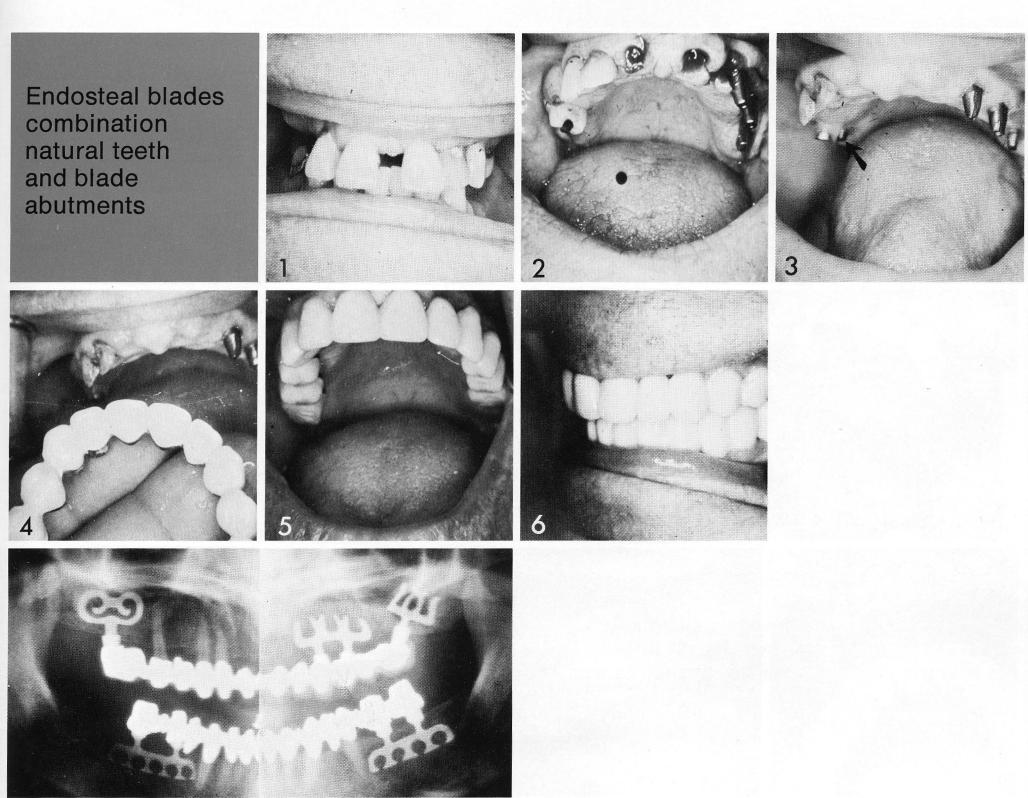

Endosteal blades

combination

natural teeth and blade abutments

Bladevents can be significant tools in providing a partially edentulous arch (1) with secure, balanced support for a fixed prosthesis. Here a double-posted anterior bladevent (2) counterbalanced natural teeth. Posteriorly (3) a tuberosity bladevent (arrow) strengthened the teeth and complemented a similarly situated bladevent on the other side of the arch.

1 Bladevent implants provide support for a maxillary fixed prosthesis